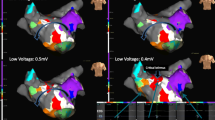

The SuperMap algorithm successfully identified the arrhythmogenic substrate in all 7 patients (100%). Three patients (43%) exhibited focal tachycardia mechanisms. One patient presented with a focal tachycardia with the earliest activation in the anteroseptal region of RSPV with a cycle length (CL) of 270 ms (Fig. 3). Ablation in the earliest site (−35 msec before P wave) led to immediate termination of the arrhythmia. Isoproterenol infusion led to the induction of a second focal tachycardia located in the anterior wall of the LA (CL = 320 ms). Ablation in the earliest site led to conversion to sinus rhythm. Pharmacological stimulation could not induce further arrhythmias in this patient. In another patient, a focal tachycardia at a CL of 400 ms was localized on the posterior wall in proximity of the LIPV. Ablation led to conversion to sinus rhythm. No further arrhythmia was induced following ablation. The last patient presented with a focal tachycardia originating from the interatrial septum in proximity of the fossa ovalis at a mean CL of 235 ms. Applications on the left side of interatrial septum in this location led to the interruption of the arrhythmia. No further arrhythmias were induced.

The remaining 4 patients (57%) exhibited reentrant tachycardias. In 3 patients the SuperMap algorithm detected mitral isthmus-dependent flutters (Fig. 4) with a tachycardia CL of 240, 270, and 420 ms, respectively. A mitral isthmus line was performed connecting the LIPV to the mitral annulus in a posterolateral position. In 1 patient additional epicardial applications were needed in the CS in order to terminate the tachycardia. Bidirectional block could be documented in all cases along the lines.

Mitral isthmus dependent atypical flutter: Panels (a), (b), (c), (d), (e), and (f) represent the electrical activation projected on the LA anatomy in different time steps throughout the full CL of the counter clock wise mitral isthmus dependent AFL. Yellow arrow is indicating the wave front. All panels show a LAO view of the LA